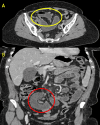

Internal hernias are an uncommon cause of small bowel obstruction (SBO). If not identified and treated promptly, they can lead to severe complications. Among these, herniation through a mesoappendix defect is exceedingly rare. To our knowledge, SBO due to a mesoappendiceal defect has only been described in a limited number of cases. In this case, a 76-year-old woman presented to the emergency department with a two-day history of acute lower abdominal pain, accompanied by nausea, vomiting, and abdominal distension. Diagnostic imaging revealed a partial small bowel obstruction with two transition points. During diagnostic laparoscopy, a loop of proximal ileum was found herniating through a mesoappendix defect, resulting in a closed-loop obstruction. The herniated bowel was viable and was successfully reduced, followed by an appendicectomy. The postoperative recovery was uneventful. This case highlights the need to consider internal hernias in the differential diagnosis of SBO, even in patients with prior abdominal surgeries.